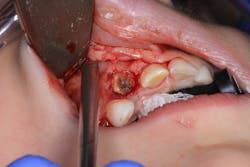

In this particular case, the patient was referred to an oral surgeon, who removed a root fragment of what was assumed to be tooth D as well as another piece of random deformed tooth structure. The cyst, along with what appeared to be tooth no. 7 (deformed), was surgically enucleated and the specimen was sent off for biopsy. Results came back as a benign dentigerous cyst. Tooth no. 8—although rotated—appeared to be unaffected.